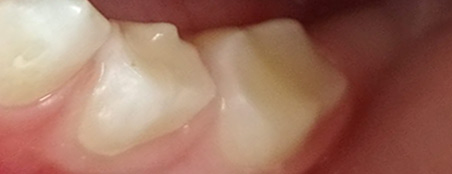

Белые пятна - это области деминерализации зуба, самые уязвимые его места, где вот-вот появится темное пятно кариеса. При побелении эмали появлении необходимо обратиться к врачу, тот подберет оптимальный метод укрепления, реминерализации тканей зуба.

Лечить зубы нужно с того момента, как в этом появилась необходимость. А вот наблюдаться желательно с момента прорезывания первого зубика или раньше, если прорезывание задерживается. Врач даст советы по уходу и питанию, а ребенок привыкнет не бояться стоматологического кресла.